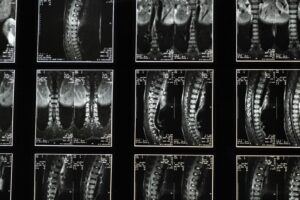

Daniel Rothenberg is a Sports Chiropractor with a Masters of Chiropractic and Masters of Exercise Science majoring in Strength & Conditioning. He works closely with a range of athletes in Brisbane and Ipswich.